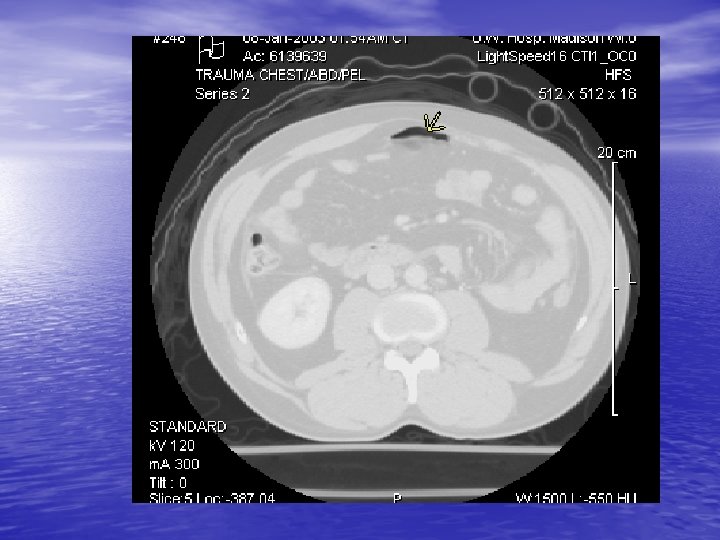

Radiology CT Cystogram § Extravasation of contrast from the bladder in both an intra and extraperitoneal distribution § Free air § Free fluid around liver

CT-Cystogram